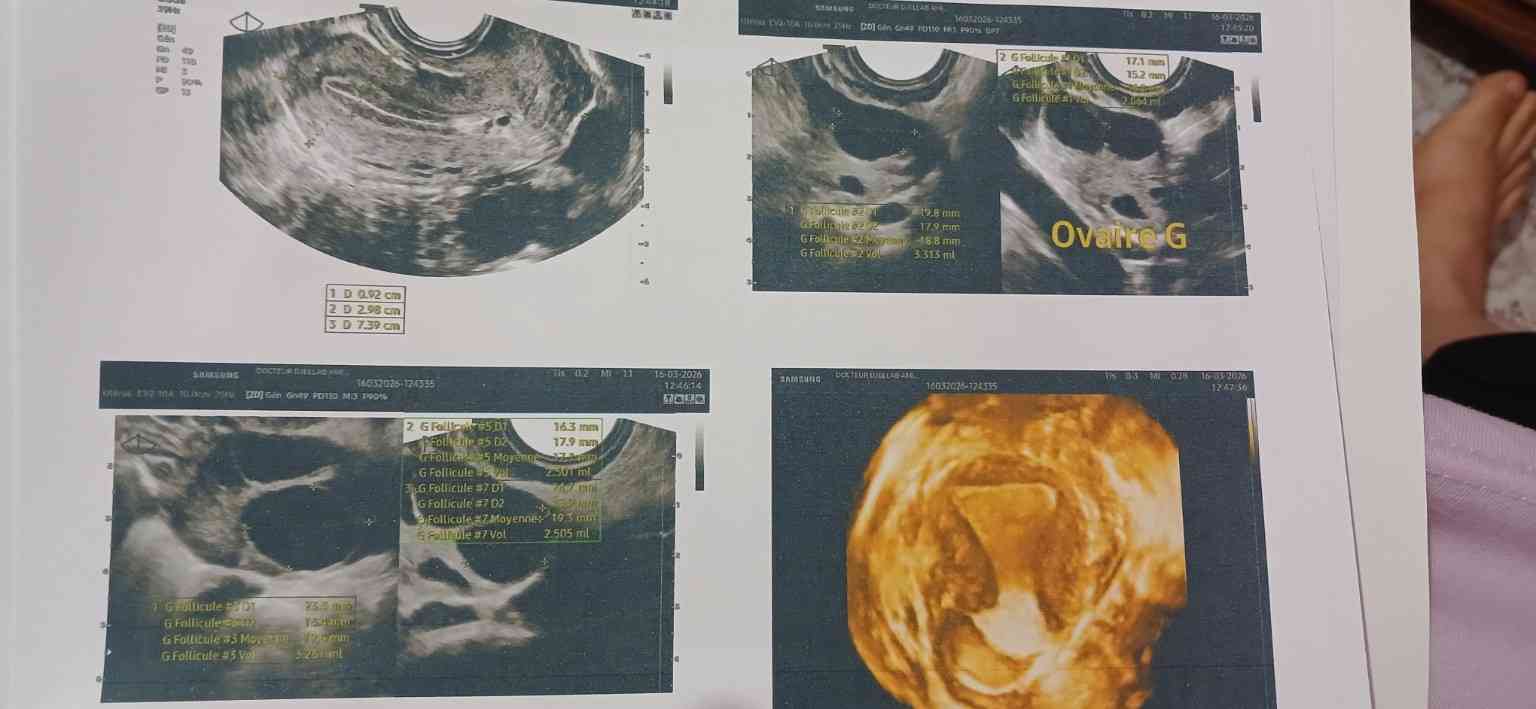

متزوجة عندي تكيس خفيف هرمون الحليب مرتفع قليلا عندي دواء cabarnex حبة كل 12 يوم عملت تنشيط و يوم 11 لقيت 5 بويضات احجامها من 17 ل 20 و لم اعمل تفجير هل احتمال الحمل مرتفع

وجود تكيس خفيف في المبايض وارتفاع طفيف في هرمون الحليب هي حالات شائعة ويمكن التعامل معها من خلال دواء الكابرنكس، وقيامك بعملية التنشيط وتحصلك على 5 بويضات بأحجام مناسبة (من 17 إلى 20 ملم) يعتبر مؤشرًا جيدًا جدًا، فهذه الأحجام تدل على أن البويضات ناضجة وجاهزة للإخصاب.

في بعض بروتوكولات علاج العقم، قد لا تكون حقنة التفجير ضرورية دائمًا، ويعتمد قرار استخدامها على عدة عوامل، منها استجابة المبايض للعلاج، وأحيانًا يتم الاكتفاء بالبويضات الناضجة الموجودة مع حدوث الجماع الطبيعي أو التلقيح الصناعي في الوقت المناسب، قد يكون الطبيب قد رأى أن البويضات جاهزة بشكل كافٍ دون الحاجة للحقنة.